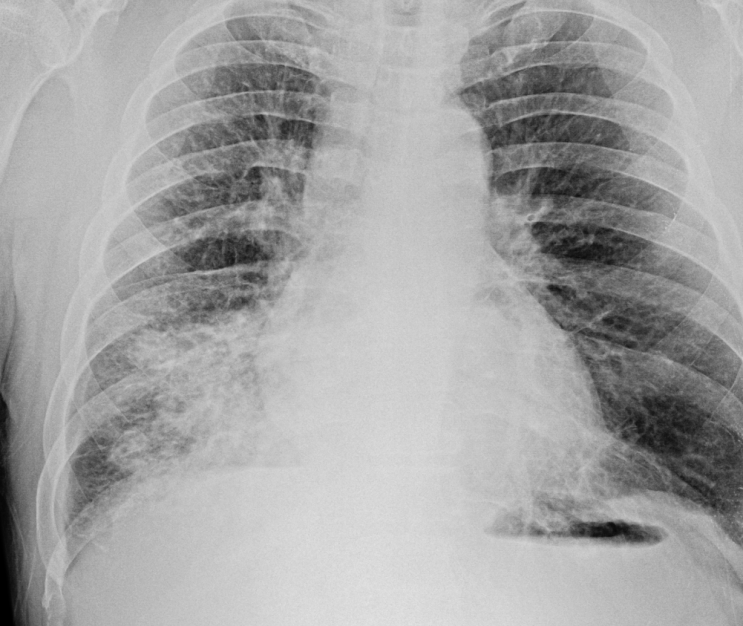

열이 없는 폐렴

2024.4.17 48/M 이사를 갔다고 몇년 만에 내원한 환자. 2달간 지속한 기침을 주소. 특이병력은 없고 기침...